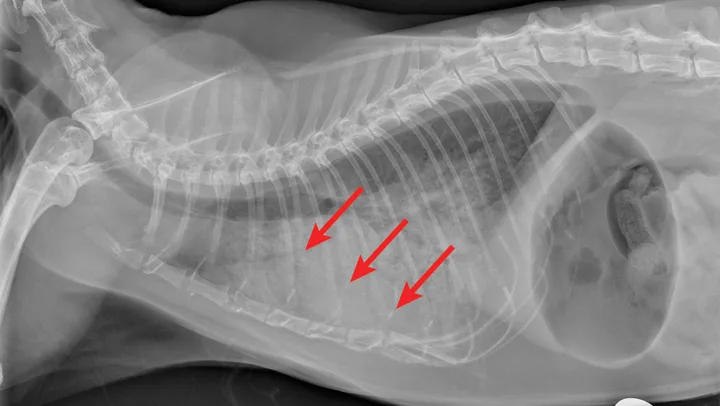

Radiographic evaluation is variable. Classic cranioventral distribution is less common in cats (Figure 3). A bronchial pattern is most common; however, bronchointerstitial, alveolar, and more structured pseudonodular patterns can occur.6,8 Occasionally, pulmonary abscesses may be appreciated and resemble pulmonary neoplasia (Figure 4).

FIGURE 3

Radiograph of bronchopneumonia with more classic cranioventral distribution (arrows). Other diseases, including CHF, have a similar distribution. Lack of this pattern does not rule out infection.